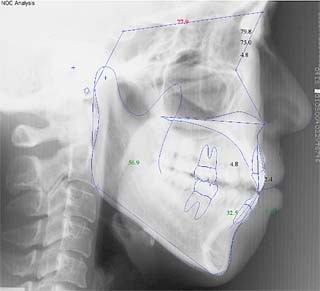

診断名:叢生を伴う開咬

年齢:28歳

使用した主な装置名:TPB、上顎リンガルブラケット矯正装置、下顎マルチブラケット装置、オーソアンカー SMAPシステム

抜歯/非抜歯および抜歯部位:非抜歯

治療期間:動的処置2年1か月、経過観察3年

本症例について検査診断の結果、開咬、叢生、下顎前突傾向を認めました。患者希望を考慮し、治療メカニクスとして、非抜歯配列、上顎のみリンガルブラケット矯正装置、下顎唇側マルチブラケット矯正装置、および、目的外使用のオーソアンカー SMAPシステムを用いることにいたしました。